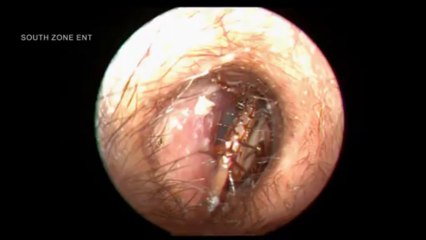

Le projet RoboRoach permet de contrôler les mouvements d'un cafard vivant avec votre propre téléphone portable. Le RoboRoach est le premier cyborg disponible dans le commerce à travers le monde, le premier insecte cyborg pour être plus exacte. Il s'agit d'un système qui utilise la neuroscience comportementale du cafard, qui utilise ses antennes de la tête pour se déplacer dans le monde qui l'entoure. Lorsque ses antennes touchent un mur, le cafard tourne le dos au mur. L'antenne d'un cafard contient des neurones qui sont sensibles au toucher et l'odorat. De ce fait, ils est "facilement" possible de contrôler les déplacement d'un cafard. Plus d'information sur la page a class="link" rel="nofollow" target="blank" href="" target="blank"Kickstartera.